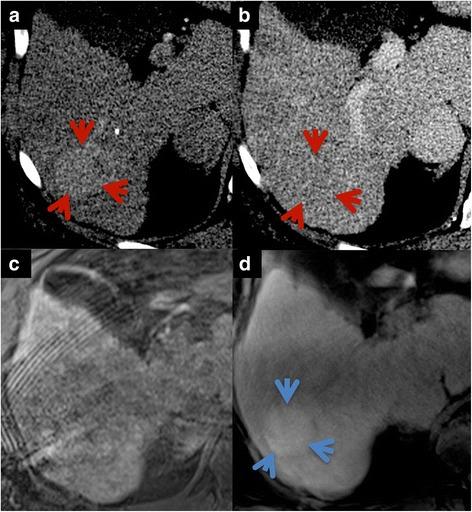

Twenty minutes after administration of a HSCA (gadoxetic acid), a T1-weighted VIBE sequence with radial k-space sampling (radialVIBE, 180 s acquisition time in free breathing) and a highly accelerated Cartesian VIBE with Dixon fat separation (CD-VIBE, CAIPIRINHA acceleration with r = 2 × 2, breath-hold 8-10 s) were acquired in 35 patients (12 female, 57 ± 13 years), who showed breath-holding difficulties in early phases of the examinations. Image quality (image sharpness, noise, artifacts, homogeneity of fat saturation, bile duct delineation and overall image quality) as well as conspicuity and liver-to-lesion signal intensity (SI) ratios of focal liver lesions were assessed for both radial- and CD-VIBE.

在给予HSCA(钆塞酸)20分钟后,对35例患者(12例女性,年龄57±13岁)进行了具有径向k空间采样的T1加权VIBE序列(radialVIBE,自由呼吸下采集时间为180秒)和具有狄克逊脂肪分离的高度加速笛卡尔VIBE序列(CD-VIBE,CAIPIRINHA加速,r = 2×2,屏气8 - 10秒),这些患者在检查早期存在屏气困难。对radialVIBE和CD-VIBE序列的图像质量(图像清晰度、噪声、伪影、脂肪抑制均匀性、胆管轮廓和整体图像质量)以及局灶性肝病变的显眼程度和肝脏与病变的信号强度(SI)比值进行了评估。

结果

两个序列的整体图像质量均被评为良好至优秀,而在大多数情况下更倾向于CD-VIBE。虽然radialVIBE在图像噪声和伪影方面获得了更好的结果,但在胆管轮廓和清晰度方面两个序列的评分相同。CD-VIBE上局灶性肝病变(n = 42)的显眼程度评分明显更高,SI比值也明显更高(radialVIBE中为1.61±0.70,CD-VIBE中为2.45±1.44,p = 0.0001)。在三名患者中,CD-VIBE由于严重的呼吸伪影被评为无法诊断,而radialVIBE在这些患者中具有诊断价值。